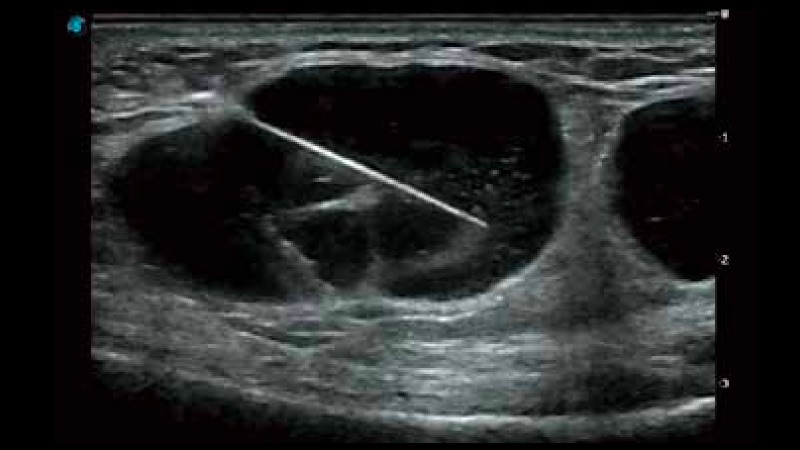

复合材料线阵探头

凭借开立医疗先进的成像技术和优异的探头技术提供的清晰的图像表现,您可以更自信地做出临床决策。